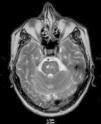

Durante su ingreso se realizó una segunda punción lumbar, obteniendo glucosa 56mg/dl, proteínas 68mg/dl y leucocitos 600/μl (90% polimorfonucleares, 10% linfocitos). Ante el hallazgo de pleiocitosis de predominio polimorfonuclear, se solicitó resonancia magnética (RMN) cerebral (fig. 1), que evidenció afectación de la protuberancia con extensión a pedúnculo cerebral izquierdo apareciendo isointenso en T1, hiperintenso en T2 (fig. 2) y flair, e hipointenso en IR T1.

Como diagnóstico diferencial radiológico cabe señalar que, por su topografía y señal, imágenes similares pueden observarse en formas iniciales de esclerosis en placas y en la encefalopatía postinfecciosa. La romboencefalitis vírica formaría parte del mismo diferencial, pero se trata de una rara entidad en la cual la lesión es única, extensa y de predominio pontino. Dados los antecedentes, el contexto clínico y las pruebas complementarias permiten orientar el diagnóstico hacia el neurobehçet.

Se ha descrito una secuencia de hallazgos en RMN en relación con la evolución de la enfermedad; así, una fase inicial con áreas de hiperintensidad en T2 a nivel del tronco cerebral, ganglios basales y hemisferios cerebrales, seguida de una fase intermedia de edema con efecto de masa y microhemorragias, y una tercera de atrofia troncoencefálica12,13. En nuestro caso, no hubo evidencia clínica pero sí radiológica de afectación troncoencefálica, correspondiéndose los hallazgos descritos en nuestro paciente con cambios iniciales.